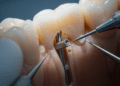

O exame clínico permite avaliar visualmente o desgaste e a presença de alterações na superfície dentária. Manifestações típicas de erosão incluem o desgaste em áreas expostas a ácido, como faces palatinas dos dentes superiores em casos de refluxo.

Nos casos mais avançados, a odontologia restauradora oferece opções como resinas compostas, facetas, coroas e outras restaurações que protegem o dente, recuperando forma e função. A escolha do material e técnica depende da extensão da erosão, da localização dos dentes afetados, da estética e da função mastigatória.